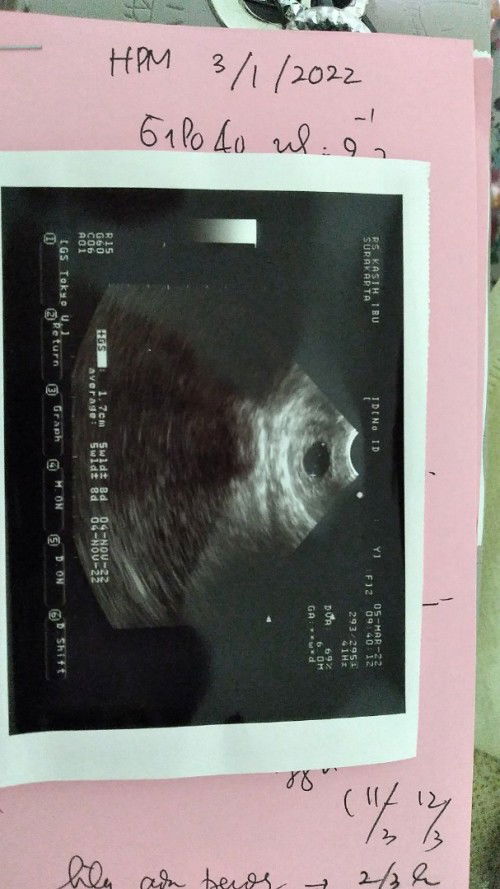

Hai moms, mau tanya dong usia dr hphtku kan terhitung sudah jalan 9 minggu, tapi minggu lalu ketika aku cek usia dr usg baru 5 minggu dan ternyata hanya ada kantong janin saja, apakah normal? Ada yg pernah ngalamin kah? Soalnya dokter bilang ini bisa jadi kehamilan kosong #seriusnanya #bantusharing